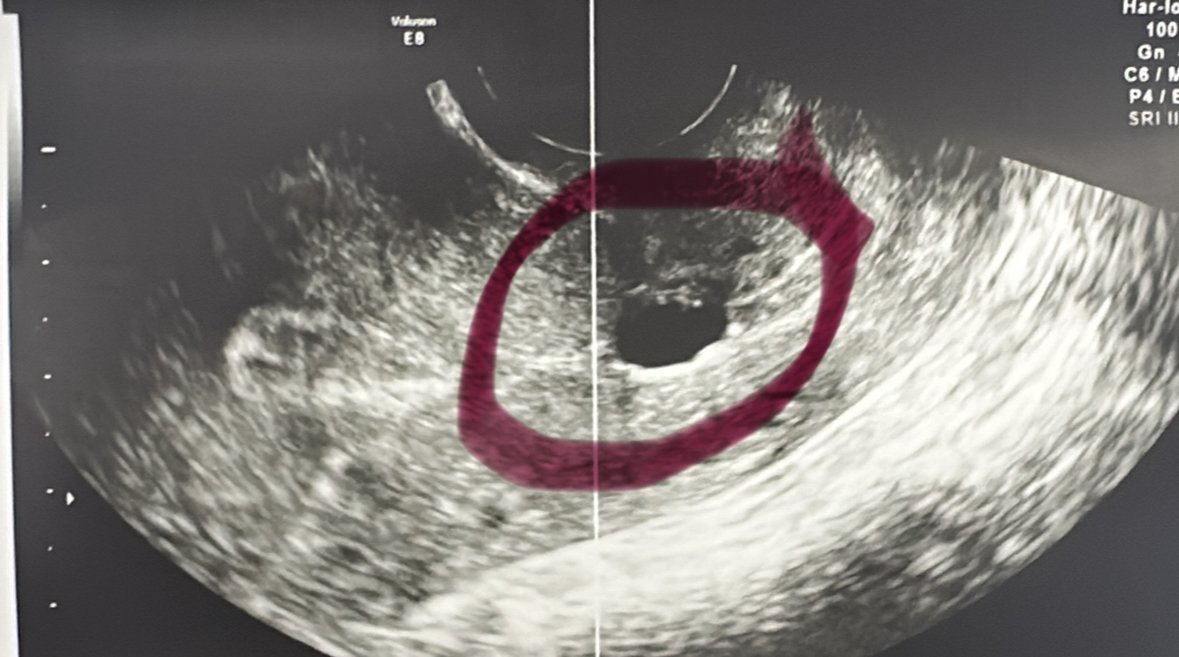

Нарастването на ЧХГ след трансфер на ембриони е важен индикатор за успешна бременност. Обикновено се очаква нивата на ЧХГ да се удвояват на всеки 48-72 часа. Нивата на ЧХГ при 13-ти ден след трансфер трябва да бъдат значително по-високи, но е важно да се следят индивидуалните показатели на всяка жена.